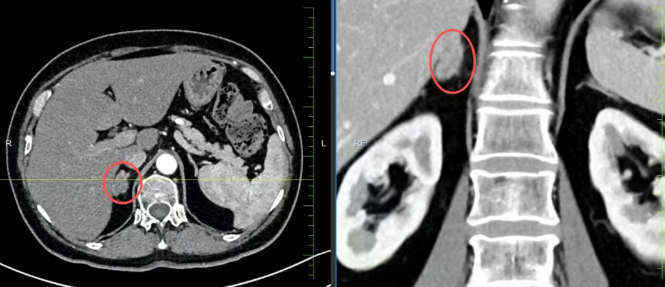

患者因右侧肾上腺肿瘤伴血肿入院,合并2型糖尿病且血糖控制不佳。长春国文医院泌尿外科依托前沿影像学检查(肾上腺CT、激素检测等),结合患者基础疾病与临床症状,实现肿瘤精准定位、性质评估及功能分型。通过多学科评估,明确手术指征与风险点,为后续治疗奠定坚实基础,为个性化治疗提供科学依据。